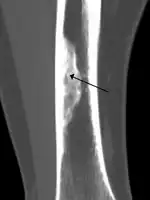

X-ray of nonossifying fibroma of distal tibia.

Diagnosis is by X-ray or MRI, usually when investigating a person for something else.[2] Medical imaging typically shows a well defined radiolucent lesion, with a distinct multilocular appearance, sometimes looking like bubbles.[2] It is usually around 1–2 cm in size, but be as large as 7 cm.[3] They consist of foci consist of collagen rich connective tissue, fibroblasts, histiocytes and osteoclasts.[2] Usually no treatment is required.[1] Surgical curettage and bone grafting may be required if it is large.[3]

It is usually diagnosed by x-ray or MRI, when investigating another problem.[1] The tumor presents as a well defined radiolucent lesion, with a distinct multilocular appearance, sometimes looking like a "soap bubble".[5] If small and no symptoms, then biopsy is not needed.[1]